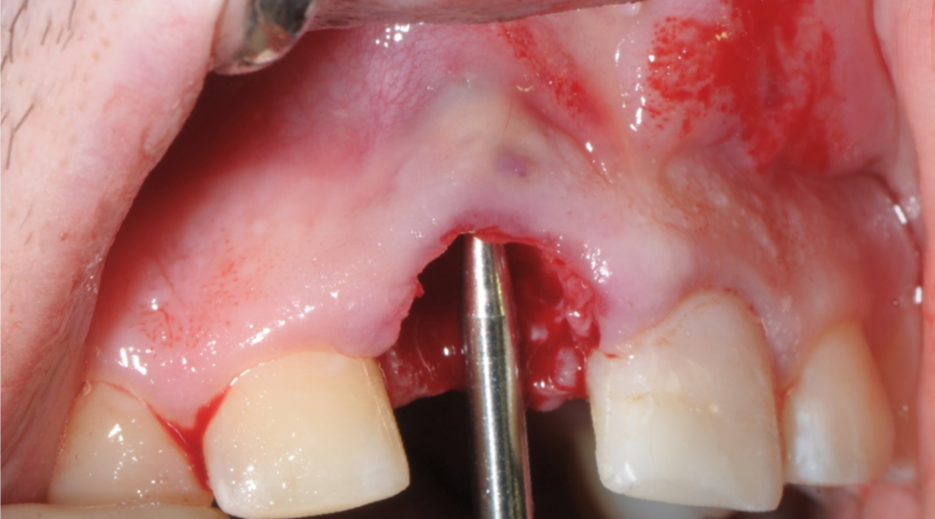

Immagine clinica iniziale ed evidenza radiografica del riassorbimento radicolare

Evidenza clinica della mancanza di parete vestibolare